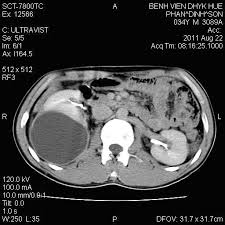

- Chụp cắt lớp vi tính (nếu cần thiết).

Hình 5. Nang đơn cực giữa thận phải trên phim CT.